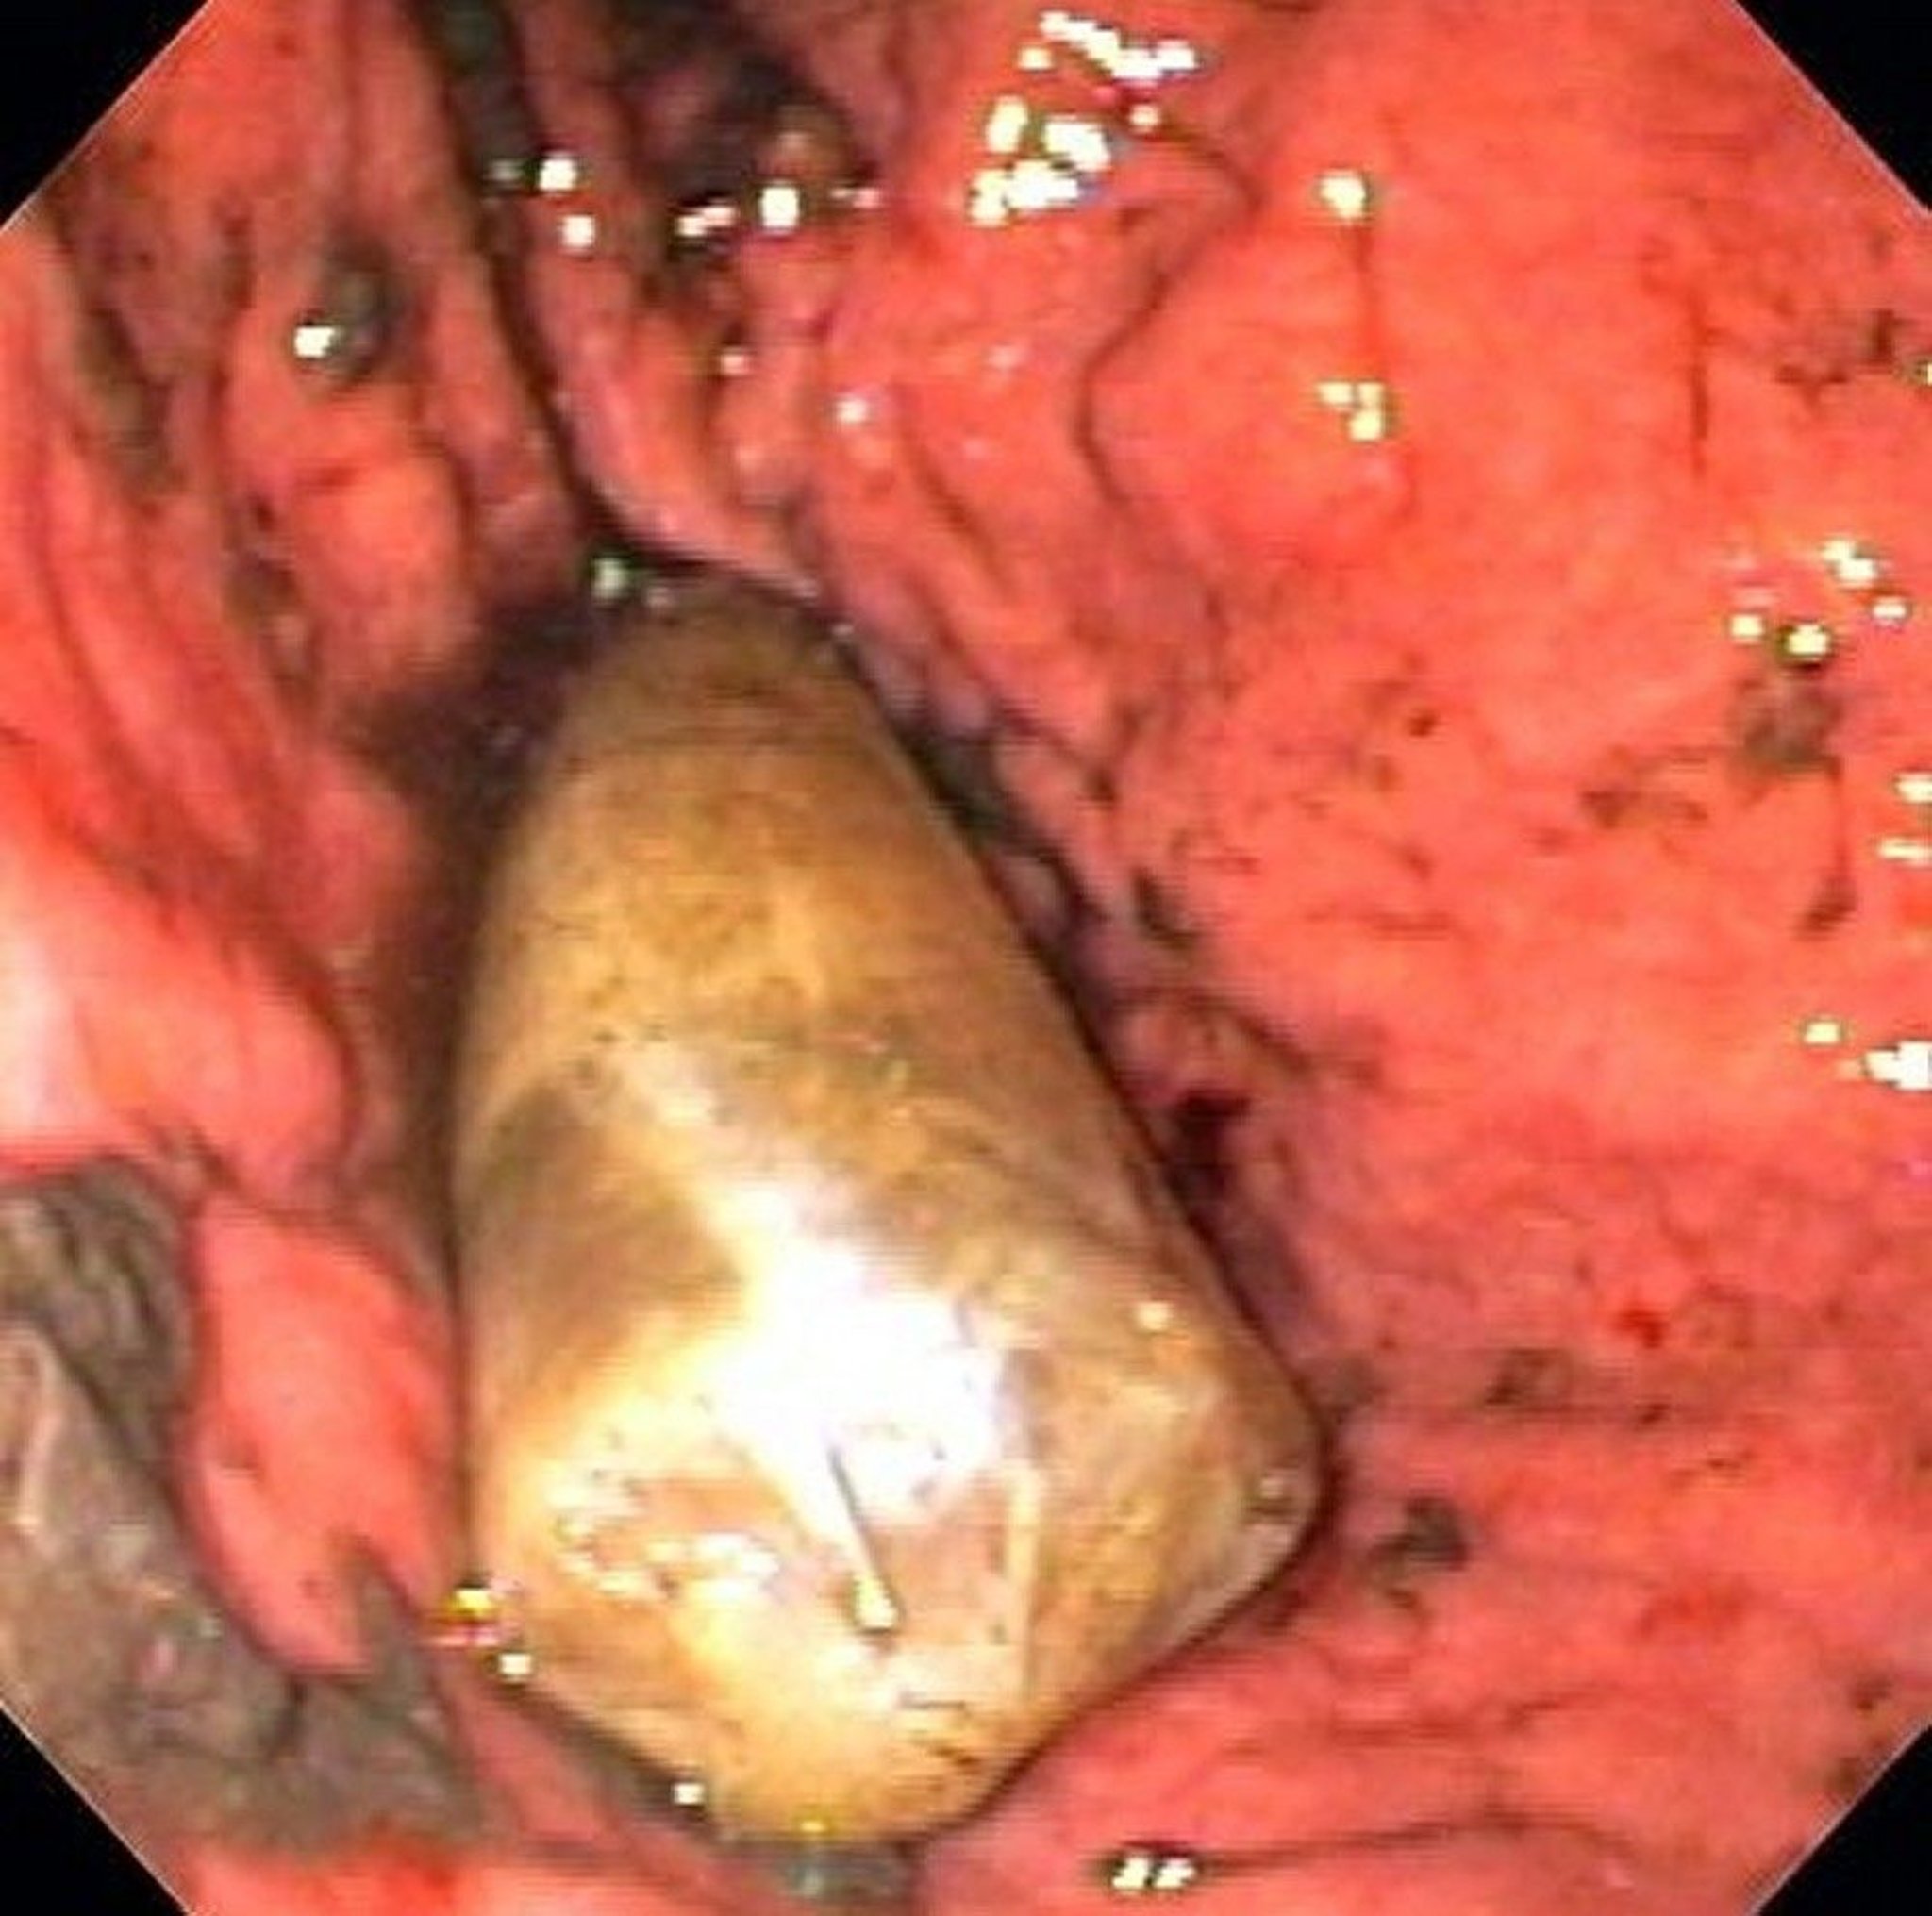

Benda Asing di dalam Lambung (Endoskopi)

Gambar ini menunjukkan kemasan obat di dalam lambung.

Gambar disediakan oleh Alan Gingold, DO.